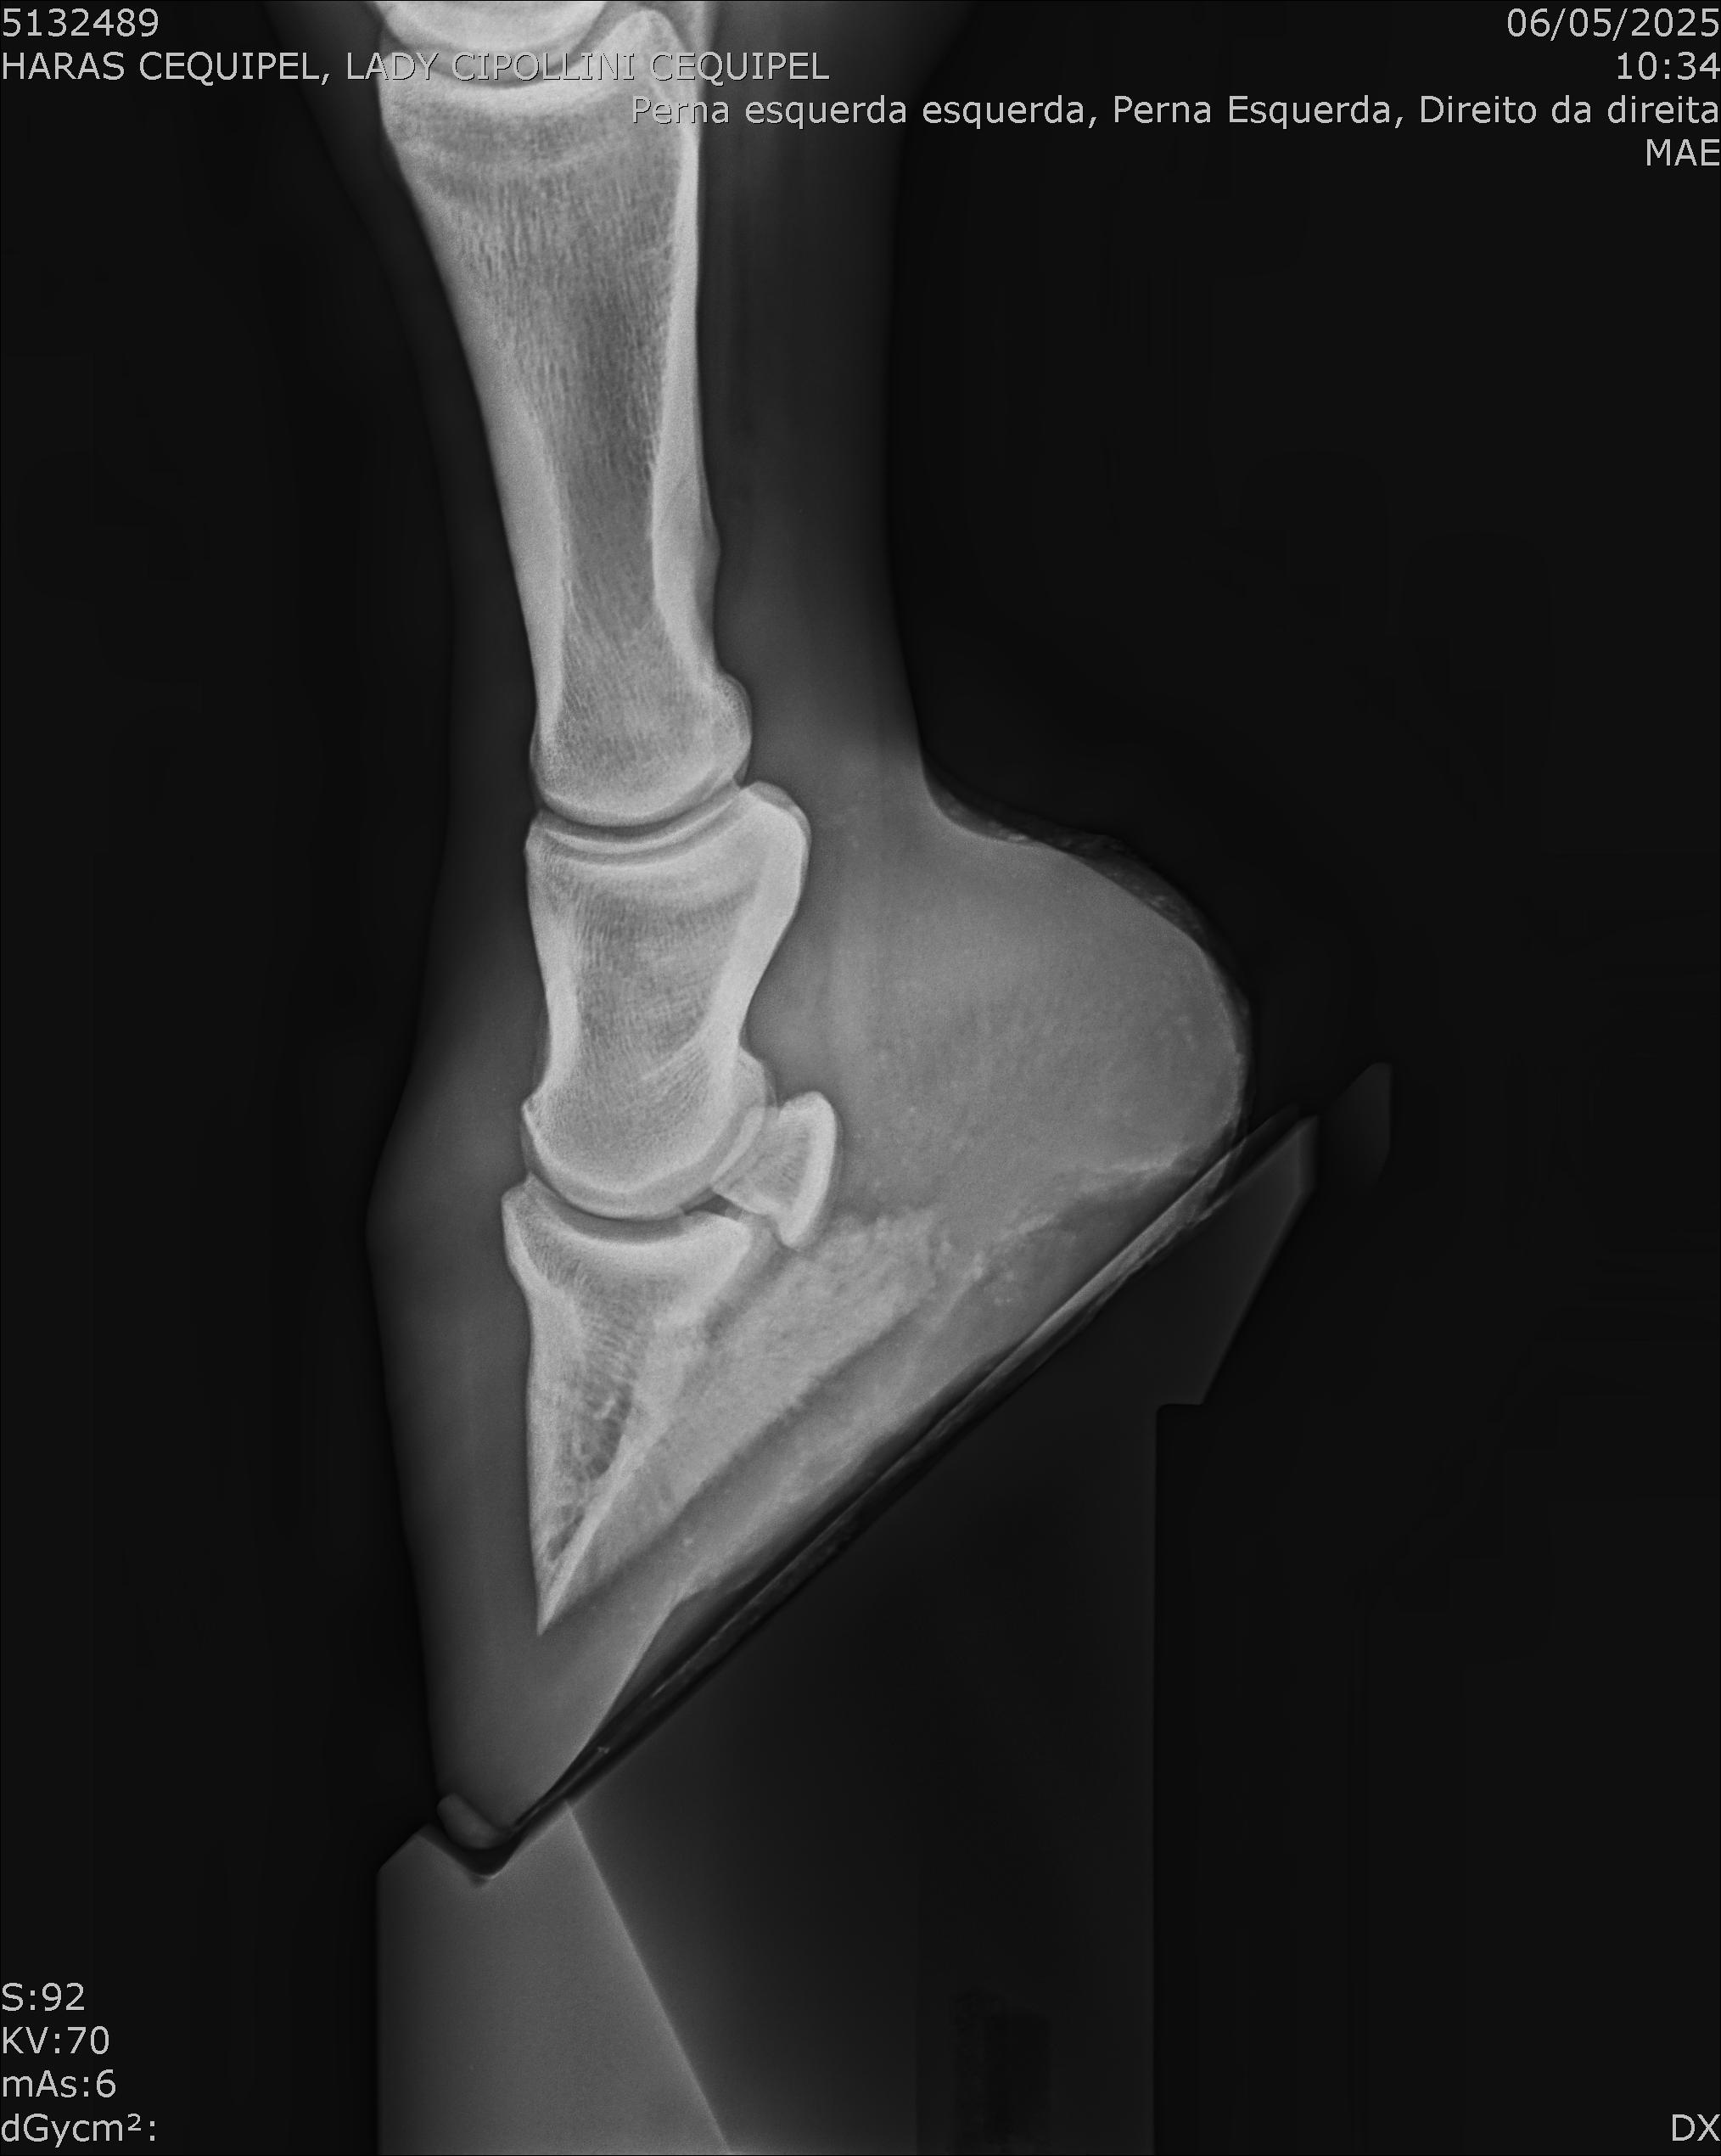

:: RAIOS-X DO LOTE